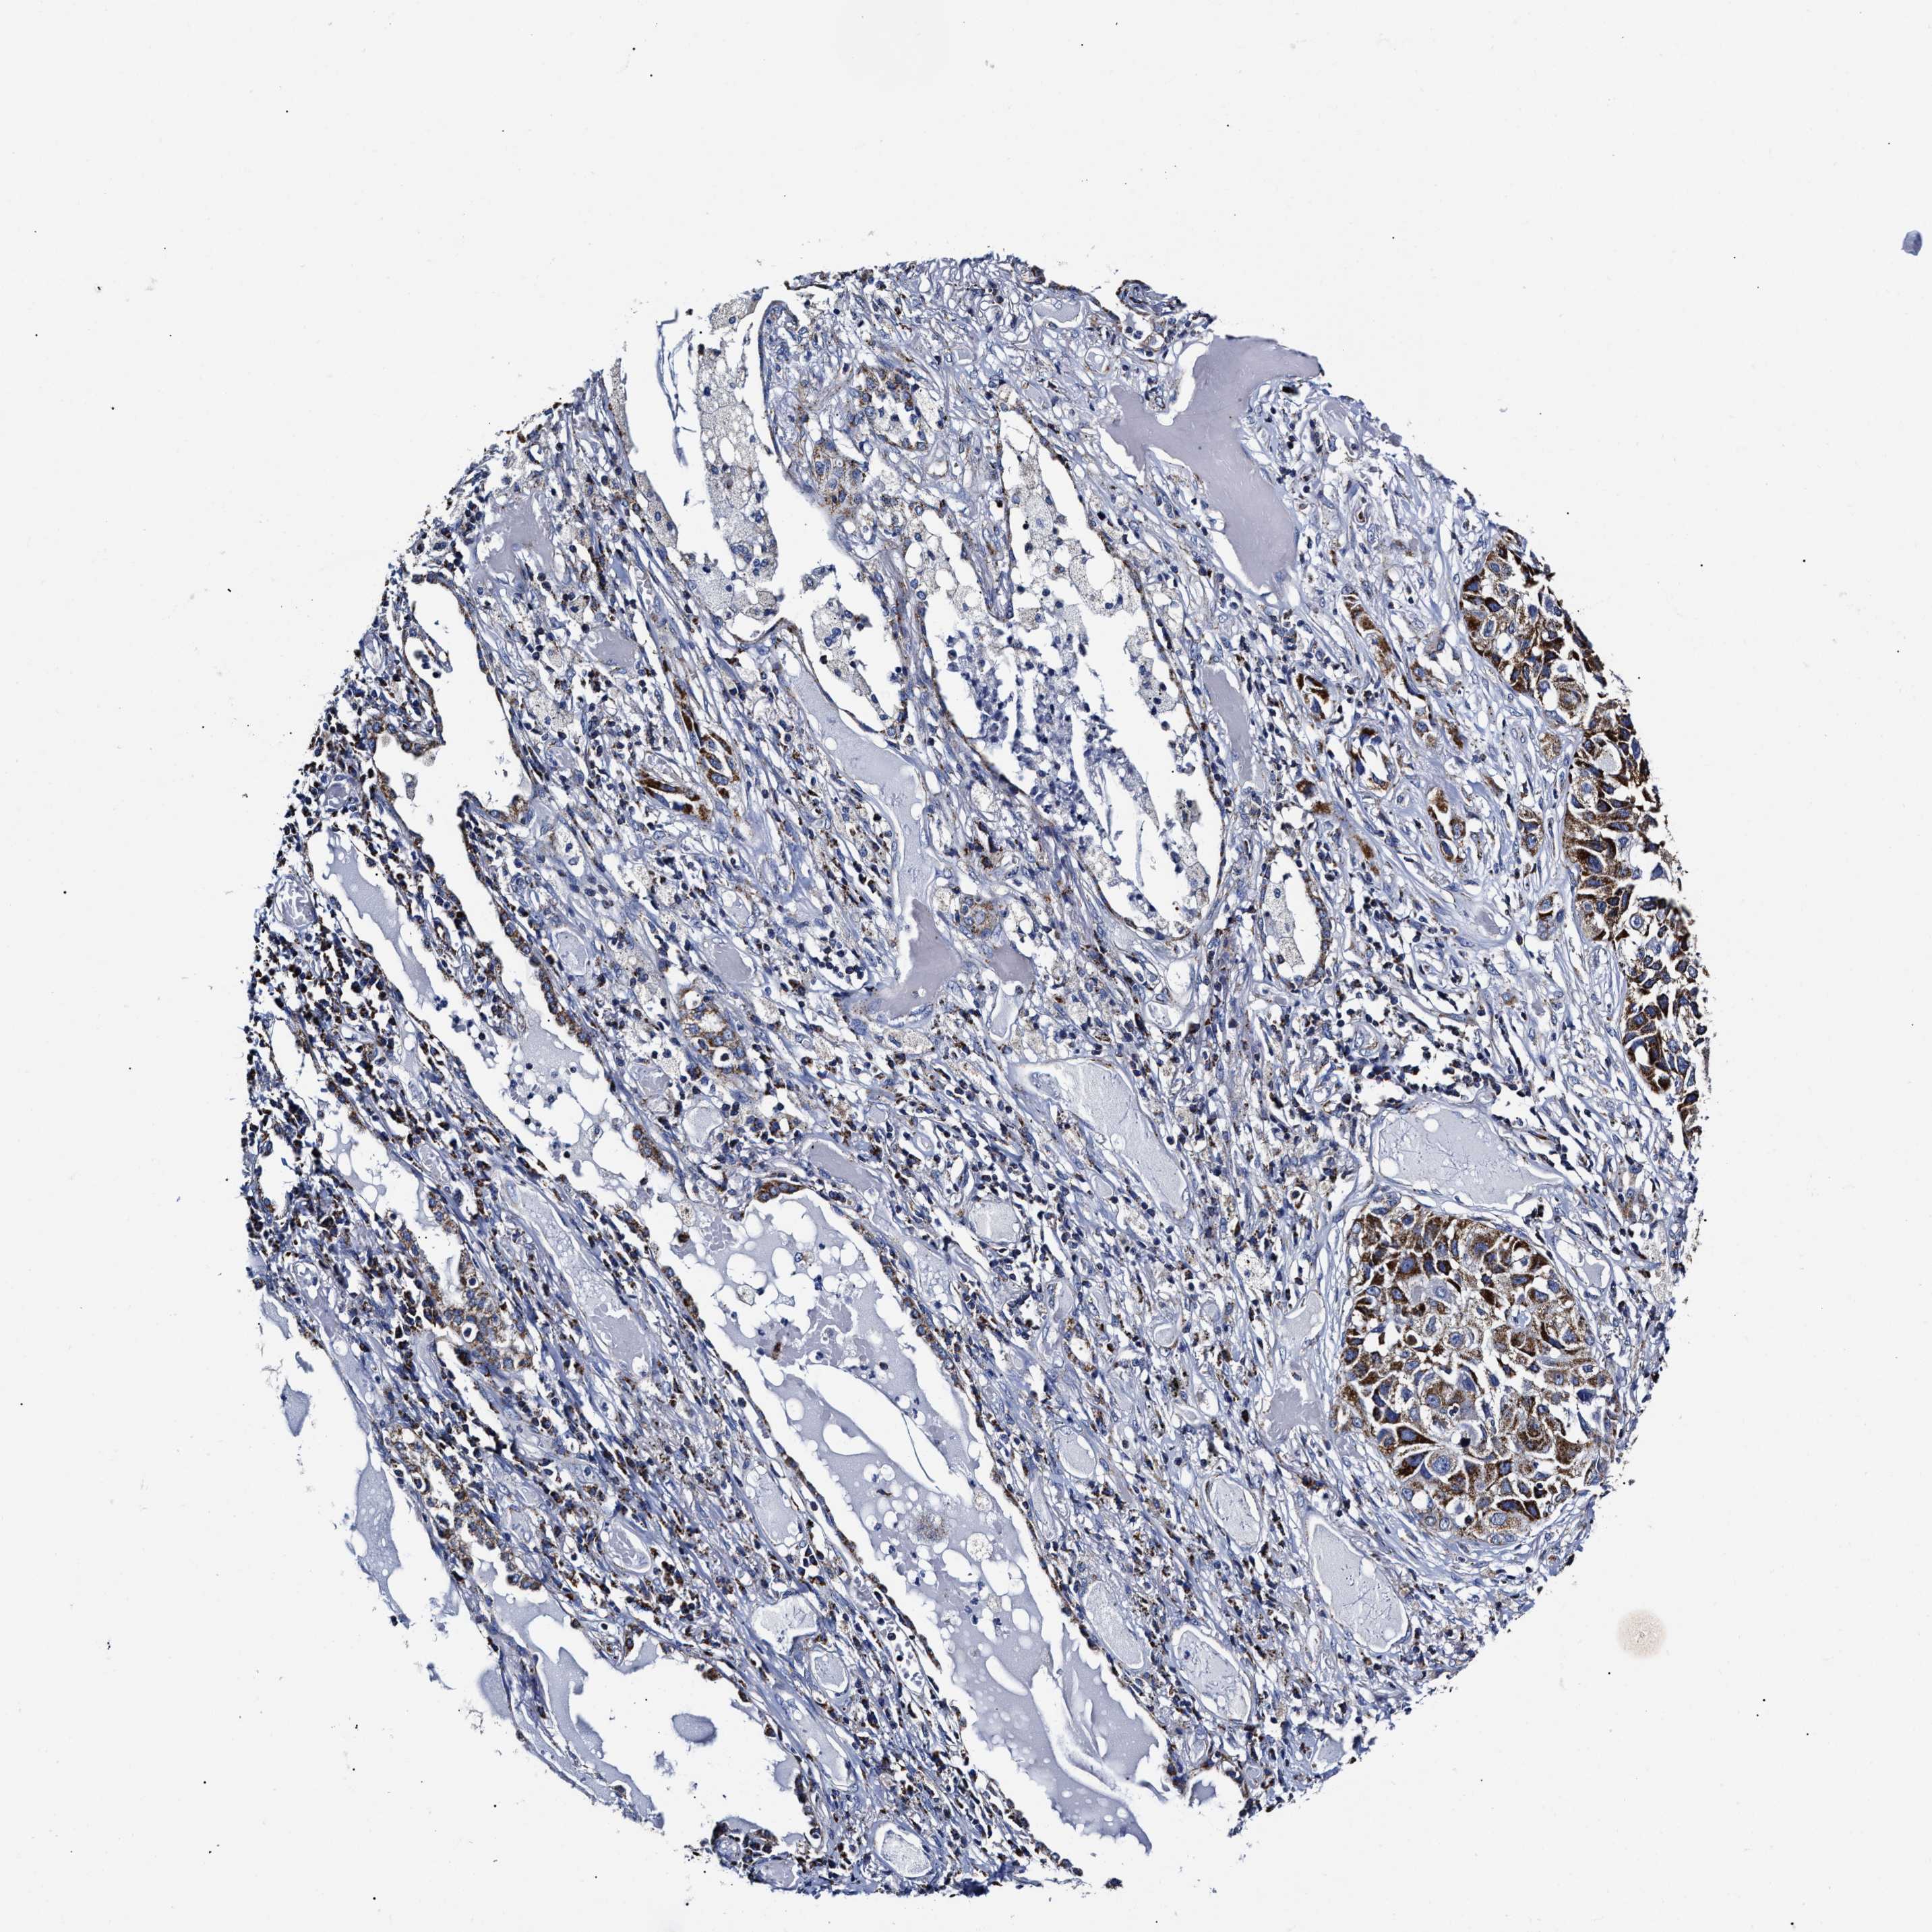

LUNG SQUAMOUS CELL CARCINOMA (TCGA) - Interactive survival scatter ploti

The Survival Scatter plot shows the clinical status (i.e. dead or alive) for all individuals in the patient cohort, based on the same data that underlies the corresponding Kaplan-Meier plots. Patients that are alive at last time for follow-up are shown in blue and patients who have died during the study are shown in red.

The x-axis shows the expression levels (FPKM) of the investigated gene in the tumor tissue at the time of diagnosis. The y-axis shows the follow-up time after diagnosis (years). Both axes are complimented with kernel density curves demonstrating the data density over the axes. The top density plot shows the expression levels (FPKM) distribution among dead (red) and alive patients (blue). The right density plot shows the data density of the survived years of dead patients with high and low expression levels respectively, stratified using the cutoff indicated by the vertical dashed line through the Survival Scatter plot. This cutoff is automatically defined based on the FPKM cutoff that minimizes the p-score. The cutoff can be changed by dragging the vertical line or by entering a cutoff value in the square labeled "Current cut-off".

Under the Survival Scatter plot the p-score landscape (black curve; left axis) is shown together with dead median separation (red curve; right axis). Dead median separation is the difference in median mRNA expression between patients who have died with high and low expression, respectively. It is calculated as follows: median FPKM expression of dead patients with high expression - median FPKM expression of dead patients with low expression. This is intended to aid the user in visually exploring custom cutoffs and the associated p-scores and dead median separation.

Individual patient data is displayed and can be filtered by clicking on one or more of the category buttons on the top of the page. Categories describing expression level and patient information include: high, low, alive, dead, female, male and tumor stages. The scale of the x-axis can be toggled between linear and log-scale by clicking on the "x log" button. Mouse-over function shows TCGA ID, patient information and mRNA expression (FPKM) for each patient.

& Survival analysisi

Kaplan-Meier plots summarize results from analysis of correlation between mRNA expression level and patient survival. Patients were divided based on level of expression into one of the two groups "low" (under cut off) or "high" (over cut off). X-axis shows time for survival (years) and y-axis shows the probability of survival, where 1.0 corresponds to 100 percent.

HINT2 is not prognostic in Lung Squamous Cell Carcinoma (TCGA)

: 28.23

P scorei

N/A

Average pTPM 51.7

Number of samples 489